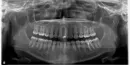

Мне отбеливали мертвый зуб, в полости канала не заходили, материал был в коронковой части зуба, верхний резец. Зуб лечили давно, старой пломбе было 15 лет. В результате цвет изменился незначительно, поставили постоянную пломбу. На снимке виден промежуток между новым материалом и каналом зуба. Снимок панорамный сделала 17 февраля 2018 г.

Это неполное заполнение пломбой зуба? Что с этим делать? Надо переустановить пломбу?

Вам необходимо обратиться к стоматологу - терапевту, который проводил отбеливание, и повторное пломбирование коронковой части зуба. Нам неизвестно каким материалами работал врач, возможно, в этом участке установлен не рентгенконтрастный материал.